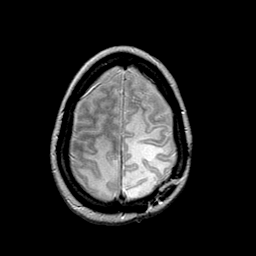

MR Study #2 -- Slice #42